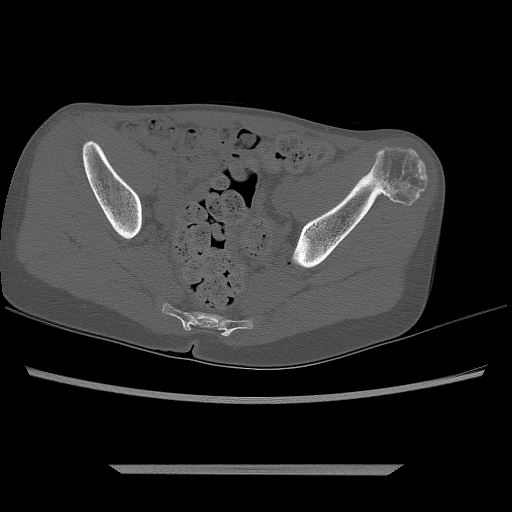

Es el tumor óseo primario benigno más frecuente con crecimiento en la superficie externa de un hueso.

Tiene cavidad medular que se continúa con la cavidad del hueso subyacente y un capuchón cartilaginoso recubriendo el espolón óseo, localizándose en metáfisis.

La localización más frecuente es en el fémur distal, y también alrededor de la rodilla o en la parte proximal del húmero.